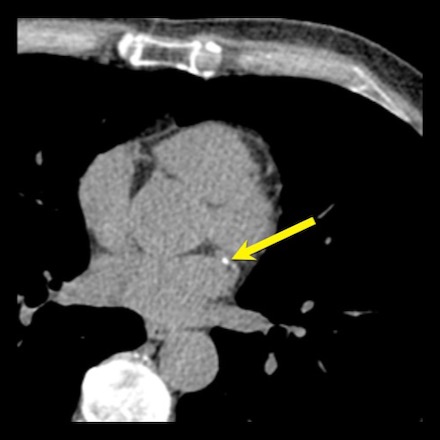

An example of positive remodeling of a non-calcified plaque in the mid RCA.

There is outward growth of the plaque with minimal stenosis of the lumen.